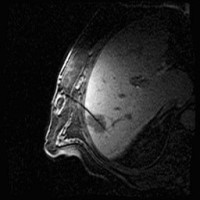

Images: Brachytherapy for liver metastases: first MRI-guided placement of one catheter per tumor followed by irradiation through the catheters using Iridium 192 radiation source.